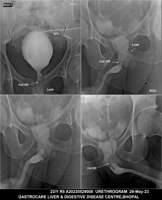

Section: URETHROGRAM Total: 95 images

BaM Enteroclysis Loopogram BaE Fistulogram Urethrogram HSG